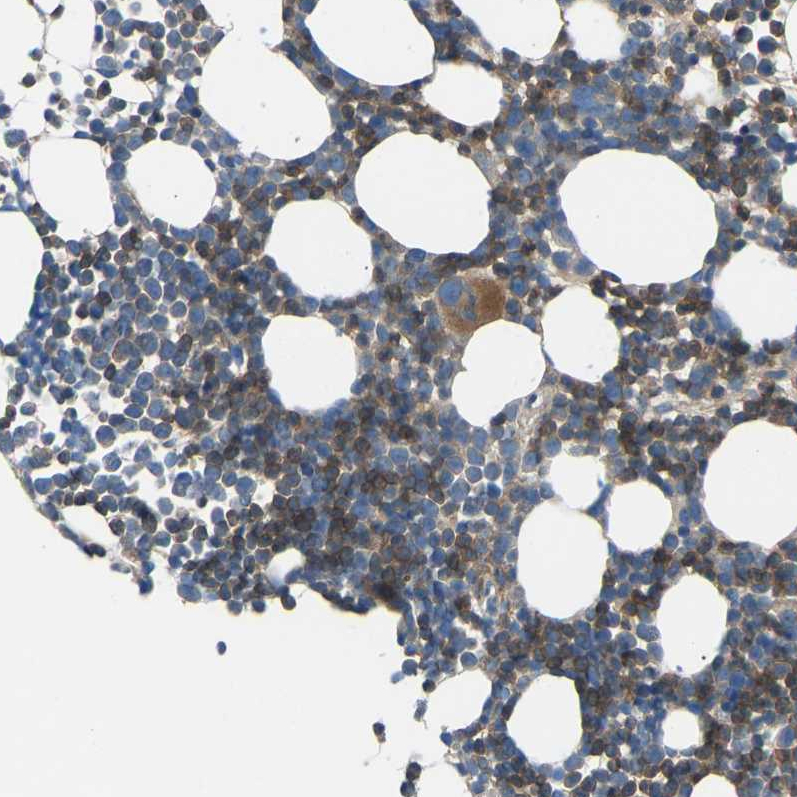

Immunohistochemical staining of human bone marrow shows moderate membranous positivity in hematopoietic cells.